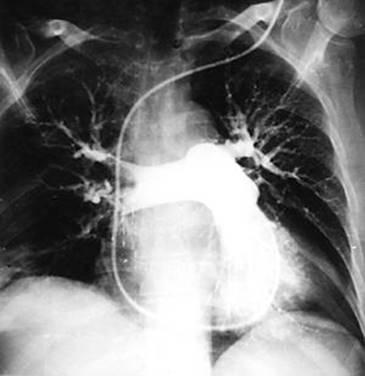

Рис. 4. Ангиопульмонограмма больного с массивной легочной эмболией. Имеется поражениеобеихглавныхлегочныхартерий